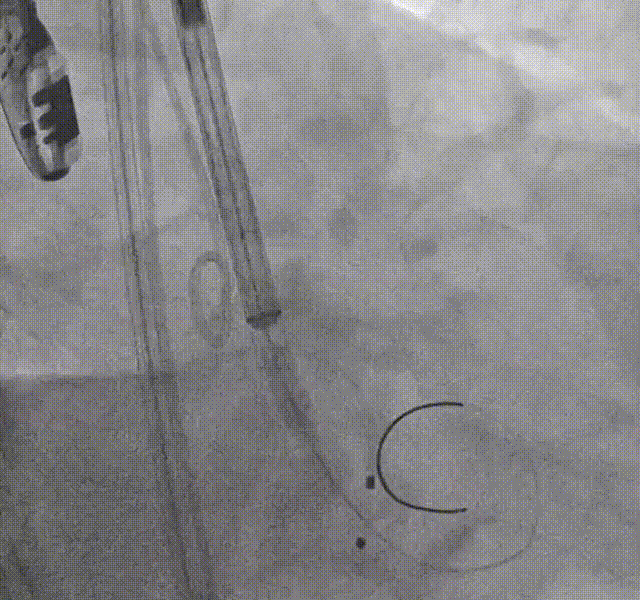

定位

初始定位

预释放后定位

首次释放弹出

再次释放

深度评估

释放体位

LAO体位

释放脱钩